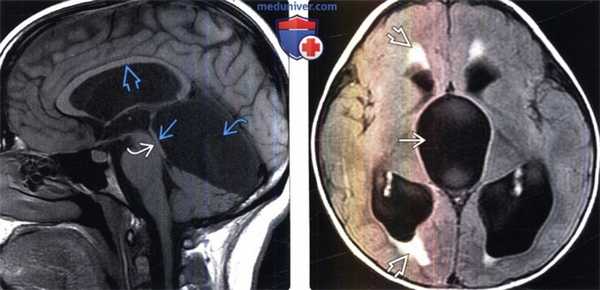

(Слева) MPT, FLAIR, аксиальный срез: у пациента с герминомой в области гипофиза определяется внутрижелудочковая обструктивная гидроцефалия с расширением III и боковых желудочков. Обратите внимание на пери вентрикулярные гиперинтенсивные зоны вследствие трансэпендимального тока СМЖ.

(Справа) MPT, Т1 -ВИ, сагиттальный срез: определяются характерные признаки стеноза водопровода мозга в виде воронкообразной формы сильвиева водопровода, отсутствия изменений со стороны IV желудочка, истончения и растяжения мозолистого тела с нисходящим смещением дна III желудочка.

(Слева) МРТ, Т2-ВИ, сагиттальный срез: определяется крупная гиперинтенсивная глиома пластинки четверохолмия, которая вызывает обструкцию водопровода мозга и расширение боковых и III желудочков.

(Справа) МРТ, постконтрастное Т1-ВИ, сагиттальный срез: в черве мозжечка визуализируется кистозный компонент с контрастированным интрамуральным узловым компонентом гемангиобластомы, что вызывает выраженную компрессию IV желудочка и обструктивную гидроцефалию.